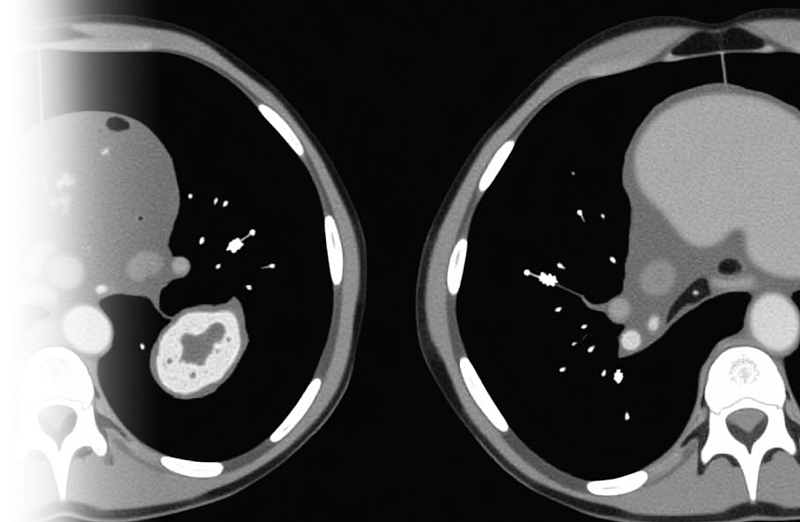

Компьютерная томография брюшной полости и забрюшинного пространства – важный метод исследования органов брюшной полости и забрюшинного пространства без введения контрастного препарата.

Для любой из вышеописанных патологий органов брюшной полости целесообразно внутривенное введение контрастного препарата за исключением узких диагностических задач.

Исследование почти всегда проводится с внутривенным контрастированием